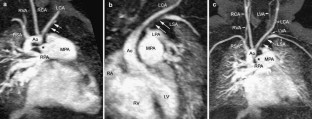

Right aortic arch with isolation of the left subclavian artery is a rare disorder. In this entity, the left subclavian artery has its origin from the pulmonary artery via the ductus arteriosus. We report an infant with an unbalanced atrioventricular septal defect, right aortic arch, bilateral ductus arteriosi and an isolated left subclavian artery. This infant also had chromosome 22q11 deletion. The origin and course of the isolated subclavian artery were well-demonstrated using contrast-enhanced 3-D magnetic resonance angiography. This non-invasive diagnostic modality can accurately reveal detailed mediastinal vascular anatomy in a young infant and allows diagnosis of aberrant vascular connections.

Fig. 1